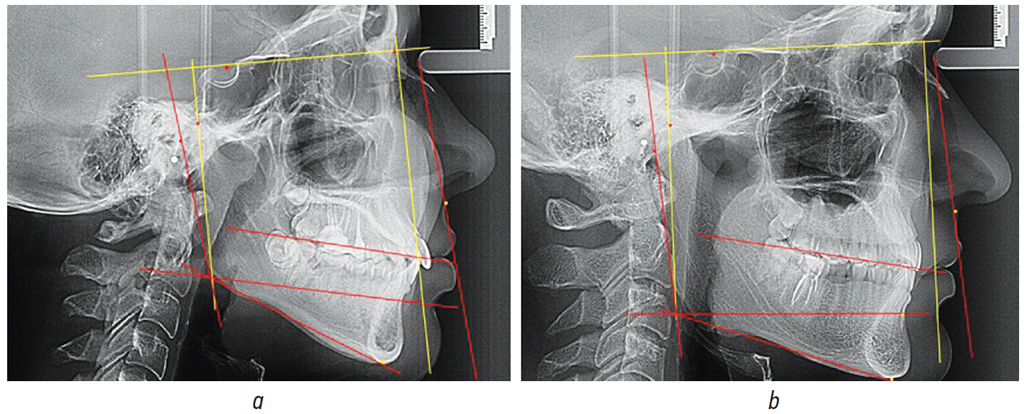

Рис. 2. Особенности расположения составных частей нижнечелюстного угла при вертикальном (а) и горизонтальном (b) типах роста челюстей

Fig. 2. Positions of mandibular angle components in vertical (а) and horizontal growth (b)

В данной группе среднее значение нижнечелюстного угла составило 126,49° ± 1,05°, что было достоверно больше (р < 0,05), чем в 1-й группе и характерно для вертикального типа роста челюстей. При этом угол касательной к ветви от гониональной вертикали (Go’-Go-Co) составил 8,18° ± 0,85°, что практически не отличалось от аналогичного показателя, полученного в 1-й группе (р > 0,05). Вторая составляющая нижнечелюстного угла, а именно угол Go’-Go-Me, равнялся 118,32° ± 1,43°, что достоверно больше (р < 0,05), чем в 1-й группе.

При анализе угла между телом нижней челюсти и ее альвеолярной частью было отмечено, что угол Go’-Go-В незначительно превышал значения 1-й группы и составлял 98,20° ± 2,64°, однако разница была недостоверной (р > 0,05). Величина угла тела нижней челюсти В-Go-Me равнялась 20,12° ± 1,94° (рис. 2, а).

Во 2-й группе угол, образованный назальной вертикалью лица и окклюзионной плоскостью, составлял 81,3° ± 3,15° и не имел достоверных различий с показателями 1-й группы. Назальная вертикаль лица образовывала с мандибулярной плоскостью угол в 61,69° ± 1,55°, что было достоверно меньше, чем в 1-й группе. Назальная вертикаль образовывала с линией В-Go угол величиной 81,79° ± 2,64°, что не имело достоверных различий с данными 1-й группы.

Таким образом, у людей с вертикальным типом роста челюстей угол отклонения ветви челюсти от гониональной линии практически не отличался от показателей 1-й группы, однако величина гонионально-ментального угла (Go’-Go-Me) была достоверно больше.

В данной группе среднее значение нижнечелюстного угла составило 115,41° ± 1,11°, что было достоверно меньше (р < 0,05), чем в 1-й и 2-й группах и характерно для горизонтального типа роста челюстей. При этом, угол между гониональной вертикалью и касательной к ветви, составил 6,67° ± 1,78°, что практически не отличалось от аналогичного показателя, полученного в других группах (р < 0,05). Вторая составляющая нижнечелюстного угла, а именно угол Go’-Go-Me, был 108,79° ± 1,72°, что было достоверно меньше (р < 0,05), чем в 1-й и 2-й группах.

Анализируя углы тела нижней челюсти с альвеолярной ее частью было отмечено, что величина угла Go’-Go-В незначительно превышала значения 1-й группы и составляла 93,94° ± 3,15°, однако разница была недостоверной (р > 0,05). Величина угла тела нижней челюсти В-Go-Me была меньше, чем в других группах и составляла 14,83° ± 1,94° (рис. 2, b).

В исследуемой группе угол, образованный назальной вертикалью лица и окклюзионной плоскостью, составлял 81,72° ± 3,81° и не имел достоверных различий с показателями других групп исследования.

Назальная вертикаль лица с мандибулярной плоскостью образовывала угол в 71,22° ± 1,71°. Назальная вертикаль образовывала с линией В-Go угол величиной 86,06° ± 3,15°, что не имело достоверных различий с данными других анализируемых групп.

Таким образом, у пациентов с горизонтальным типом роста лица угол отклонения ветви челюсти от гониональной линии практически не отличался от показателей 1-й группы, однако величина гонионально-ментального угла (Go’-Go-Me) была достоверно меньше (рис. 2, b).

Рис. 3. Особенности расположения составных частей нижнечелюстного угла при мезиальной (а) и дистальной (b) окклюзии

Fig. 3. Positions of mandibular angle components in mesial (а) and distal occlusion (b)

При исследовании телерентгенограмм с мезиальной окклюзией, установлено, что отличительной особенностью является увеличение угла отклонения ветви нижней челюсти от гониональной вертикали. Средняя величина угла Go’-Go-Co составляла 18,03° ± 1,22°, что характеризовало гнатическую форму мезиального соотношения зубных рядов.

Для дистальной окклюзии характерно уменьшение угла Go’-Go-Co менее чем на 5°. При гнатических формах аномалий окклюзии отмечалась непараллельность назально-субназальной вертикали и касательной к ветви челюсти.